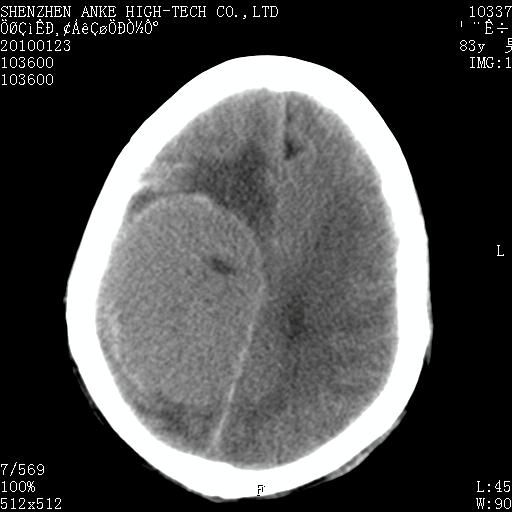

患者:男,83岁,突发意思不清2天。原有脑梗塞病史。

肿瘤卒中,考虑恶性,依次淋巴瘤、转移瘤、恶性脑膜瘤、胶质母等,建议mri。

肿瘤卒中,考虑恶性脑膜瘤可能性大。

脑膜瘤多见于老年女性,与雌激素水平有关。本例虽为老年男性,但是本例还是考虑脑膜瘤的可能性大。

镰旁脑膜瘤卒中